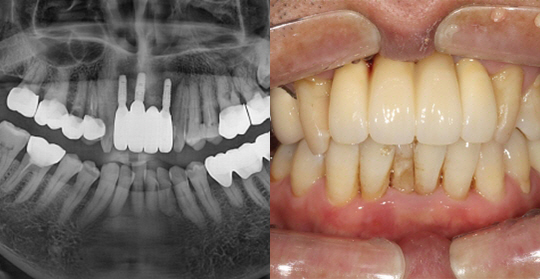

(50세 남 환자)